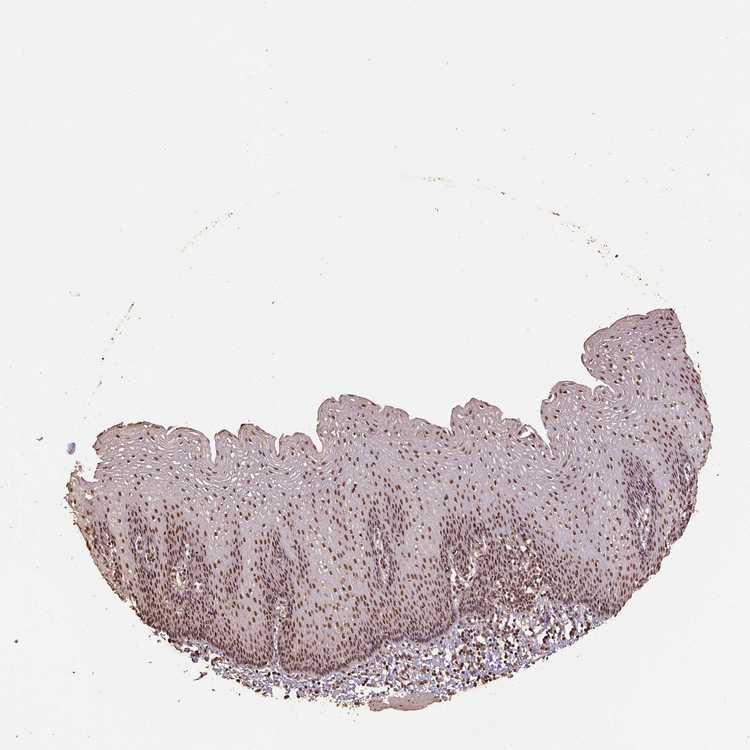

ESOPHAGUS - Antibody stainingi

Antibody staining in the annotated cell types in the current human tissue is reported as not detected, low, medium, or high, based on conventional immunohistochemistry profiling in selected tissues. This score is based on the combination of the staining intensity and fraction of stained cells.

Each image is clickable and will lead to virtual microscopy that enables deeper exploration of all samples and also displays staining intensity scores, fraction scores and subcellular localization as well as patient and tissue information for each sample.

Antibody HPA021238Antibody HPA062245Antibody CAB069927

Squamous epithelial cells HighMediumHigh